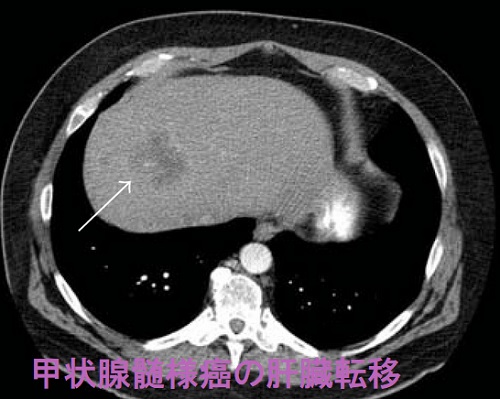

甲状腺髄様癌の肝臓転移も多く報告されています。単純CTで石灰化を認める場合があります。(Diagn Cytopathol. 2015 Jan;43(1):45-8.)(Tokai J Exp Clin Med. 2020 Apr 20;45(1):18-23.)(Int J Surg Case Rep. 2021 Oct;87:106419.)

大腸がん、胃がん、乳がん、卵巣がんなど、粘液産生性癌の肝臓転移は、色々なパターンの石灰化を認めます。微細な砂粒状石灰化を認めることが多いです。

甲状腺髄様癌の肝転移巣が、視床下部で産生されるはずのコルチコトロピン放出ホルモン(副腎皮質刺激ホルモン放出ホルモン:CRH)を分泌し、クッシング症候群を起こした報告があります。(Hormones (Athens). 2008 Jul-Sep;7(3):259-62.)